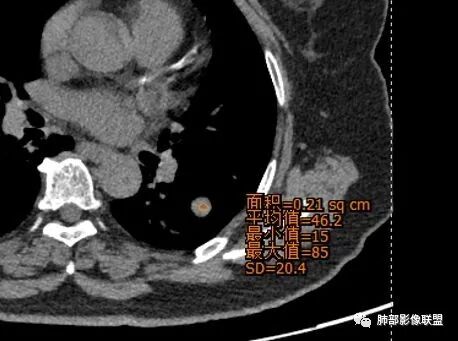

定位 左肺下叶背段斜裂旁实性小结节,边界清晰,密度尙均匀,未见脂肪钙化,与支气管关系不密切,可见肺血管贴边,增强呈轻中度强化,平扫47hu 动脉期48 静脉期67hu,

定性 常规考虑 良性结节,错构瘤或PSP可能,鉴别类癌,神经源性肿瘤,巨淋巴结增生,建议追观或穿刺活检。

CT值46H

增强67HU

其实强化还算是中度,幅度超过20HU

●CT上,60%病例可见脂肪密度(CT值-40~-120HU),由于通常含有脂肪、软骨、纤维组织和上皮成分,肿块的CT值离散度大。

●强化方式取决于错构瘤的内部的成份,如果含脂肪及软骨成份较多,血管含量少,血供不丰富,CT增强仅表现为轻度强化或无明显强化;当含平滑肌及腺体成分多时,可出现较明显的强化,但少见。

●错构瘤虽然是良性肿瘤,但有时它也会缓慢生长,逐渐增大,周围血管也会出现推移,所以也会出现“血管贴边征”。